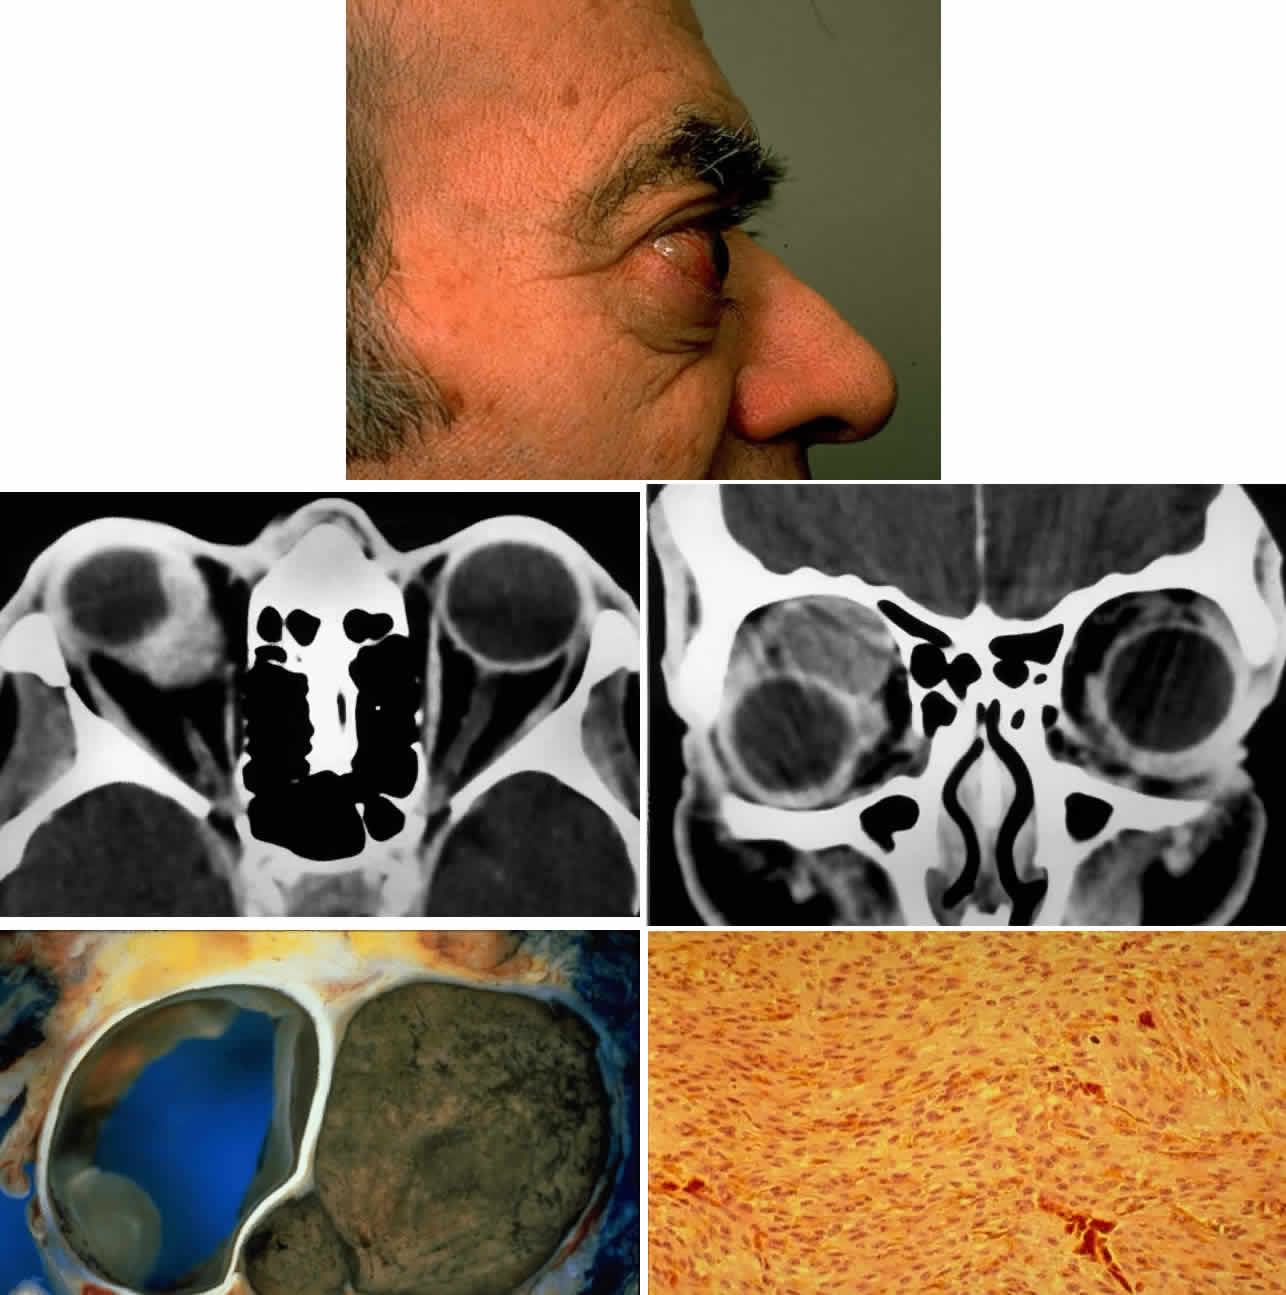

Fig. 13. A 65-year-old man presented originally with a right retinal detachment and secondary glaucoma due to a large choroidal melanoma. The patient refused enucleation and self-treated instead with herbal medicines and “health foods.” He presented again 6 years later with acute onset of proptosis associated with pain, periocular edema, erythema, and marked restricted ductions (A). CT scan revealed the intraocular tumor, with massive orbital extension and displacement of the globe anteriorly, downward, and laterally (B and C). He underwent lid-splitting exenteration and split-thickness skin graft from the anterior thigh. The gross specimen shows the massive orbital component of melanoma, which had extended from the posterior choroid through emissarial vessels (D). An area of predominantly spindle-shaped melanoma cells with scattered, heavily pigmented macrophages is shown (E) (H & E, × 200). (D and E courtesy of Valerie A. White, MD, Department of Pathology, University of British Columbia, and the Vancouver Hospital and Health Sciences Center.)